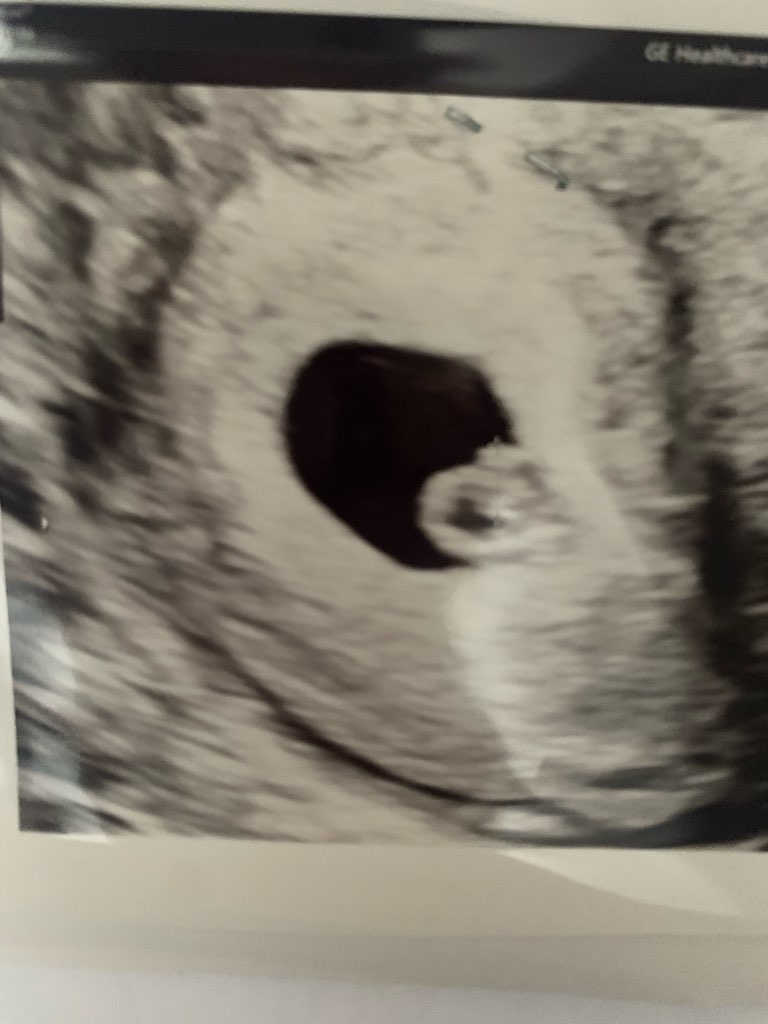

A to mój kropek z bijącym serduszkiem 🥰🥰🥰☺️

Załączniki

• IMG_7511.jpeg

IMG_7511.jpeg

65,7 KB · Wyświetleń: 78